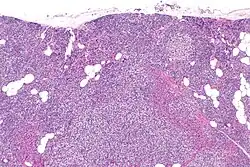

Primary hyperplasia of the parathyroid gland, results from both hypocalcaemia and increased phosphate levels by decreasing expression of calcium sensing receptors and vitamin D receptors at the parathyroid gland.[8][4] These decreases in receptor expression lead to hyperfunctioning of the parathyroid. Hyperfunction of the parathyroid gland is thought to exacerbate primary hyperplasia which evolves further to a secondary more aggressive hyperplasia. Histologically, these hyperplasic glands can be either diffuse or nodular.[24] Primary hyperplasia, usually resulting in diffuse polyclonal growth is manly related to reversible secondary hyperparathyroidism. Secondary hyperplasia of the parathyroid gland is more often a nodular, monoclonal growth that sustains secondary hyperparathyroidism and is the catalyst in the progression to tertiary hyperparathyroidism. Nodular hyperplastic glands in tertiary hyperparathyroidism are distinctly larger in both absolute size and weight up to 20-40-fold increases have been reported.[25][26][24]

Parathyroid glands are normally composed of chief cells, adipocytes and scattered oxyphil cells.[27][14] Chief cells are thought to be responsible for the production, storage and secretion of parathyroid hormone. These cells appear light and dark with a prominent Golgi body and endoplasmic reticulum. In electron micrographs, secretory vesicles can be seen in and around the Golgi and at the cell membrane. These cells also contain prominent cytoplasmic adipose.[27][14] Upon onset of hyperplasia these cells are described as having a nodular pattern with enlargement of protein synthesis machinery such as the endoplasmic reticulum and Golgi. Increased secretory vesicles are seen and decreased intercellular fat is characteristic.[27][24] Oxyphil cells also appear hyperplasic however, these cells are much less prominent.

Biochemically, there are changes in function between normal and nodular hyperplastic parathyroid glands. These changes involve proto-oncogene expression and activation of proliferative pathways while inactivating apoptotic pathways.[28] In nodular parathyroid tissue increased expression of TGF-a, a growth factor, and EGFR, its receptor, results in aggressive proliferation and further downregulation of vitamin D receptors, which act to suppress hormone secretions.[25][8][28] Furthermore, the proliferative marker, Ki67 is seen to be highly expressed in the secondary nodular hyperplastic state.[28][25] Tumour suppressor genes have also been highlighted as being silenced or degraded in nodular hyperplastic parathyroid tissue.[8][28] One such gene, p53, has been shown to regulate multiple tumour suppressor pathways and in tumorigenesis can be degraded by b-catenin. This pathway, in some aspect, is mediated by CACYBP, which is highly expressed in nodular parathyroid hyperplasia.[28]